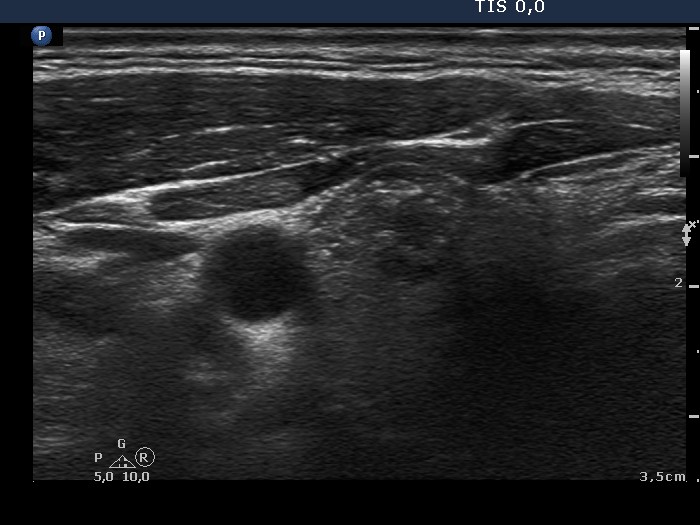

Papillary carcinoma (histology) - case conp047

Transverse scan

Longitudinal scan

The primary tumor focus (signed with red arrows) was 4 mm in maximal diameter in histopathology. Scattered echogenic punctate granules (microcalcifications) are pointed with yellow arrow. The tumor invaded the normal parenchyma.